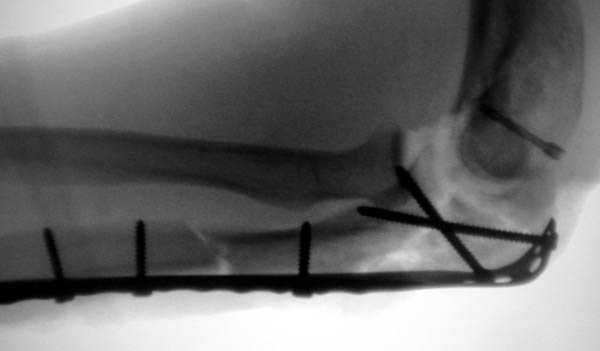

Здесь выставлены несколько случаев и варианты фиксации локтевого отростка, некоторые в комбинации с другими переломами.

1 вариант применен ACUMED локинг пластина

2 вариант

перелом локтевого отростка с переломом головки лучевой кости (использованы 2 мм шурупы)